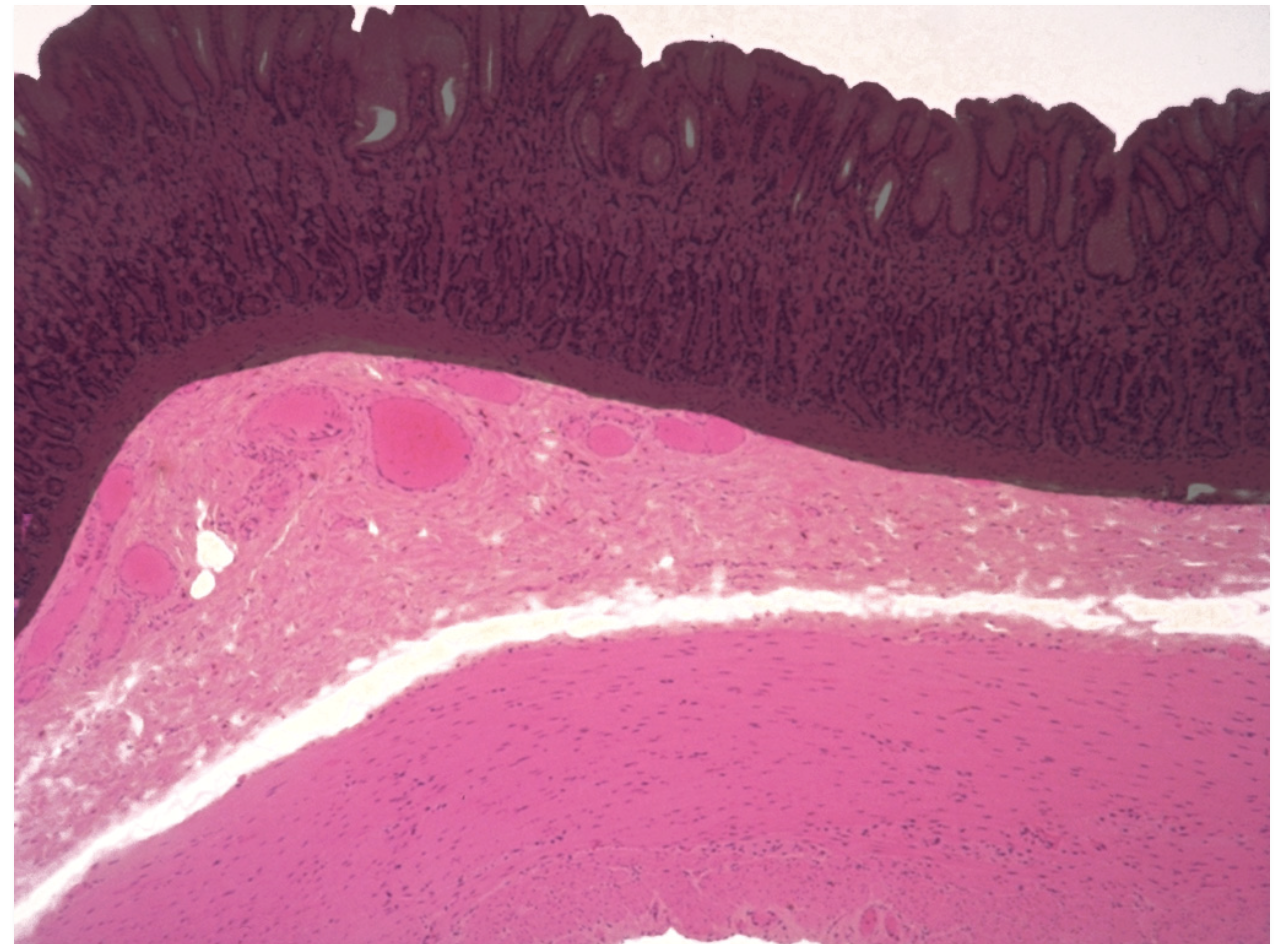

large intestine lacks __ but has an abundance of __

large intestine lacks villi but has an abundance of intestinal glands (secretes mucus for lubrication of feces)

large intestine’s mucosal surface consists of a single layer of __

absorptive cells (removes water from feces)

this image is of what structure

small intestine

colon (large intestine)